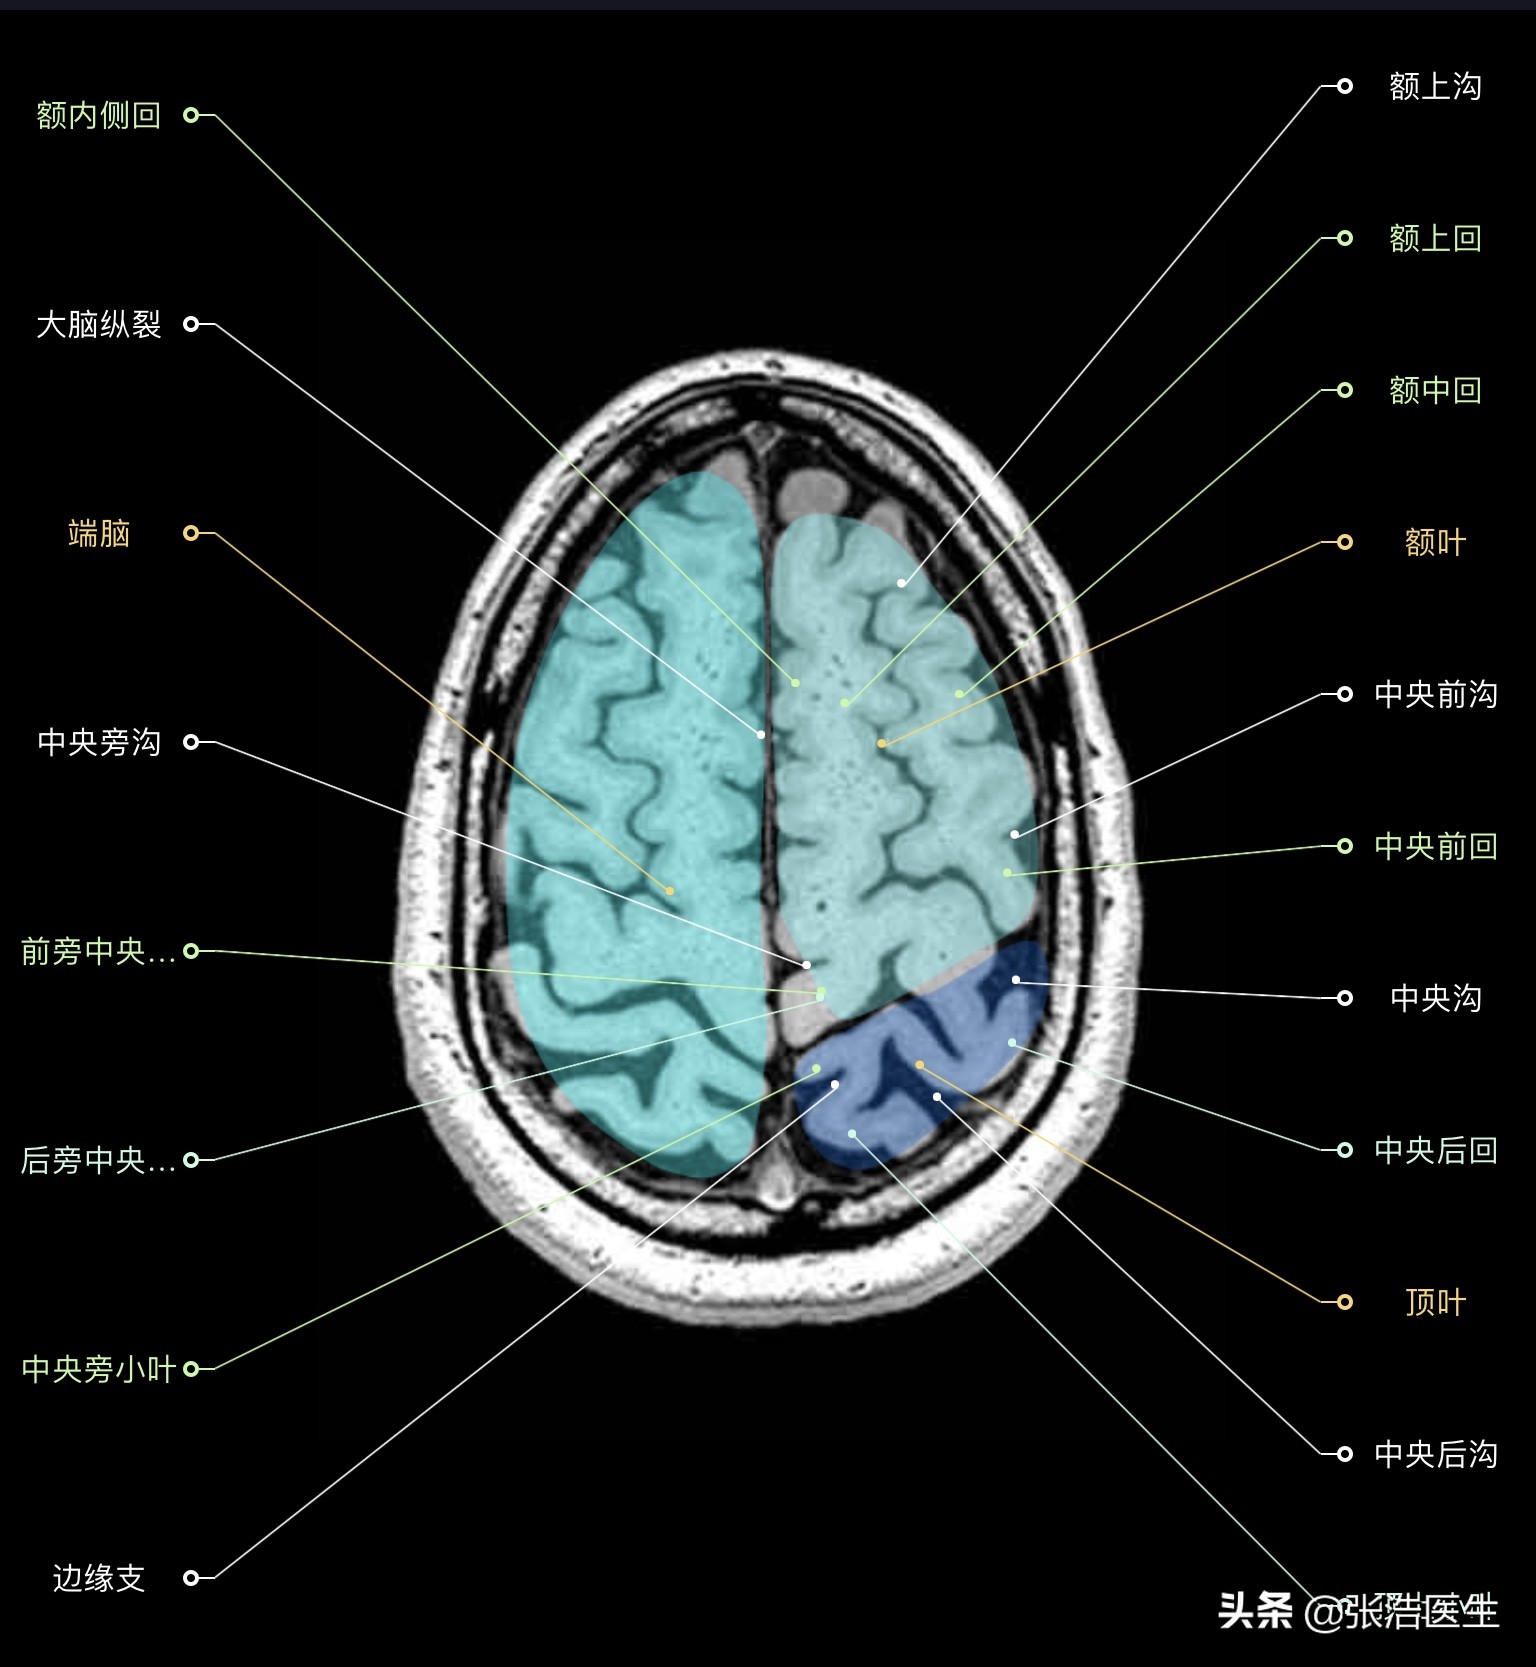

颅脑MRI横断面高清解剖图谱(图层2)